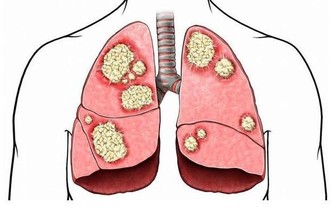

3、中風

引起手麻的另一常見疾病便是中風。凡人初覺大指、次指麻木不仁或不用者,三年之內有中風之疾。

雖然手指麻木不一定會發生中風,但對於年齡在40歲以上的中年人來說,如果經常出現頭痛、眩暈、頭重腳輕、肢體麻木、舌頭髮脹等症狀,且患者平時又有高血壓、高血脂、糖尿病、腦動脈硬化等疾病時,應多加以注意,警惕中風的發生。